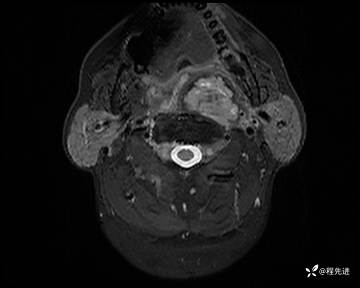

MRI平扫+增强:

T2压脂: